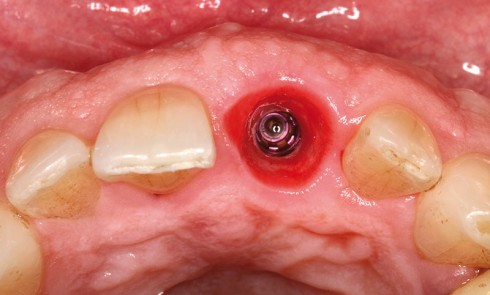

Réalisation d’un bridge céramométallique maxillaire sur implant et d’un bridge provisoire antagoniste Cas clinique des Drs Guillaume Drouhet et Thibault...